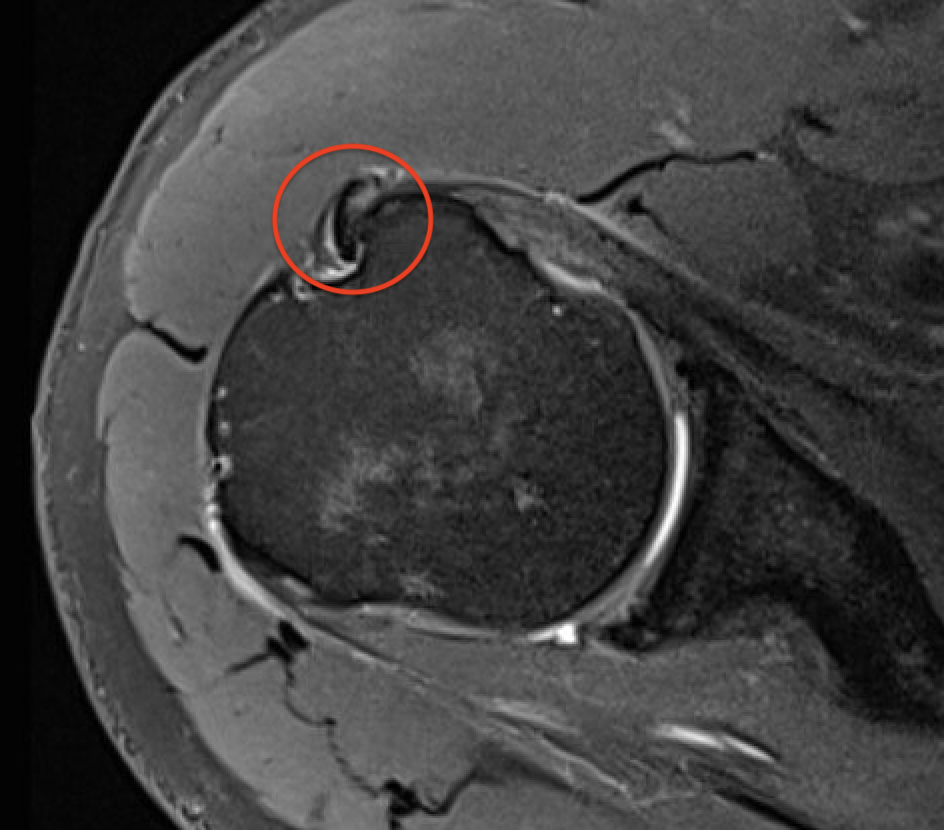

Perched long head of biceps with tear of upper border of subscapularis

Full thickness minimally retracted subscapularis tear